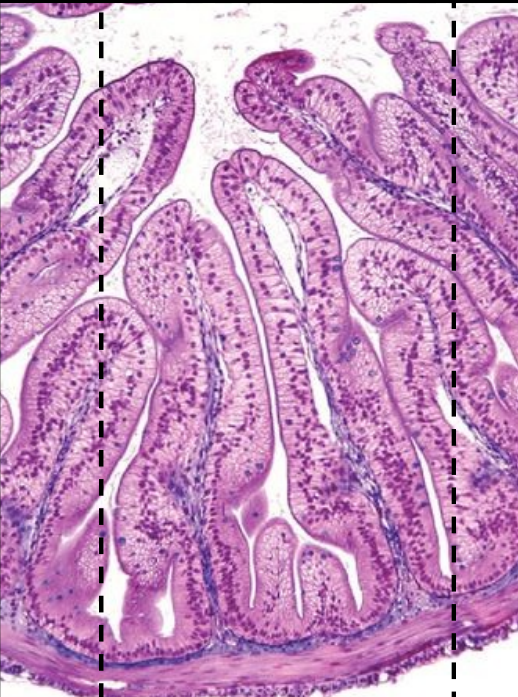

Un zoom sur l’intestin grêle

Dans l’intestin grêle sont récupérées les petites molécules issues de l’estomac (qui a cassé les grosses molécules des aliments) en nutriments (protéine, glucides كَرْبُوهَيْدرات et lipides الدهون) assimilables par l’organisme d’autrant plus que sa forme favorise un échange maximal avec le sang.